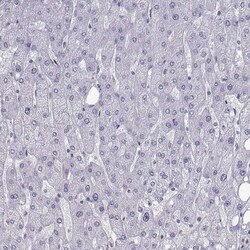

- Main image

- Experimental details

- Immunohistochemical analysis of C16orf59 in human liver using C16orf59 Polyclonal Antibody (Product # PA5-84253) shows no positivity in hepatocytes as expected.